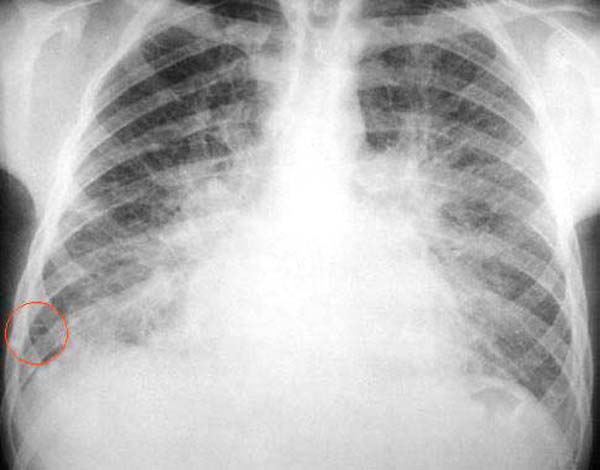

Es llamativo el aumento de tamaño del corazón y el engrosamiento de la trama vascular y relleno alveolar que irradian simétricamente desde los hilios, lo que sugiere una insuficiencia cardíaca con congestión pulmonar pasiva. En la base de la pared costal derecha se pueden ver una sombras lineales finas (1-2 mm) de menos de 2 cm de largo, paralelas y dispuestas perpendicularmente a la pleura costal denominadas líneas B de Kerley o septales, que son mas perceptibles en la ampliación de la zona (Placa 21-A).

PLACA 21-A

Las líneas de Kerley se deben al engrosamiento de tabiques interlobulillares que, en este caso, se debe a edema. También pueden producirse por infiltración neoplásica o , con menor frecuencia , por inflamación.